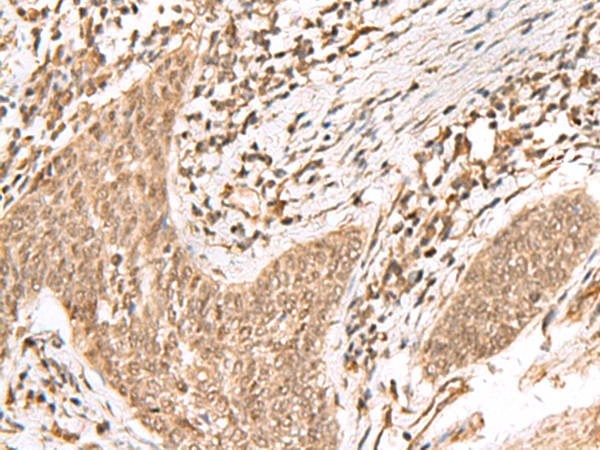

IHC positive control: |

Human lung cancer and Human esophagus cancer |

IHC Recommend dilution: |

50-300 |